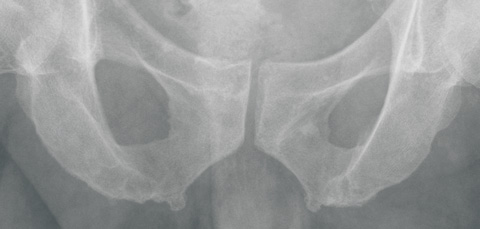

When the remains at St Thomaskirche were transferred to a new coffin in 1949, surgeon Wolfgang Rosenthal had the opportunity to inspect the skeleton. Although he did not notice any special features of the skull, he detected multiple bony outgrowths, which he considered to be exostoses, on the pelvic ring.3 He claimed His had mistaken these for signs of “arthrosis deformans” (osteoarthritis). He also noticed overdeveloped Muskellinien (“muscle lines”; bony outgrowths at sites of muscle and ligament attachment, now termed enthesophytes) on the arms of the skeleton. These outgrowths were assumed to be a sign of physical strength in people who use their arms powerfully over a long period. Rosenthal stated that multiple exostoses on the arms and legs are generally found in horseback riders, soldiers and sportsmen, in response to repetitive mechanical trauma. At that time, such formations were termed Reiter- und Exerzierknochen (“horseback rider and military drill bones”). A modern interpretation of these lesions is shown in Box 2.

A second part of our investigation was to reproduce the research reported by Rosenthal. We undertook a study to explore the presence of enthesophytes in modern-day organists. Details are shown in Box 3.

In 1949, surgeon Wolfgang Rosenthal noticed exostoses on the skeleton and on x-rays of 11 living organists and proposed a condition, Organistenkrankheit, which he interpreted as evidence that the skeleton was Bach’s.

Also, our study of the pelvic x-rays of 12 living professional organists failed to find evidence for the existence of Organistenkrankheit.